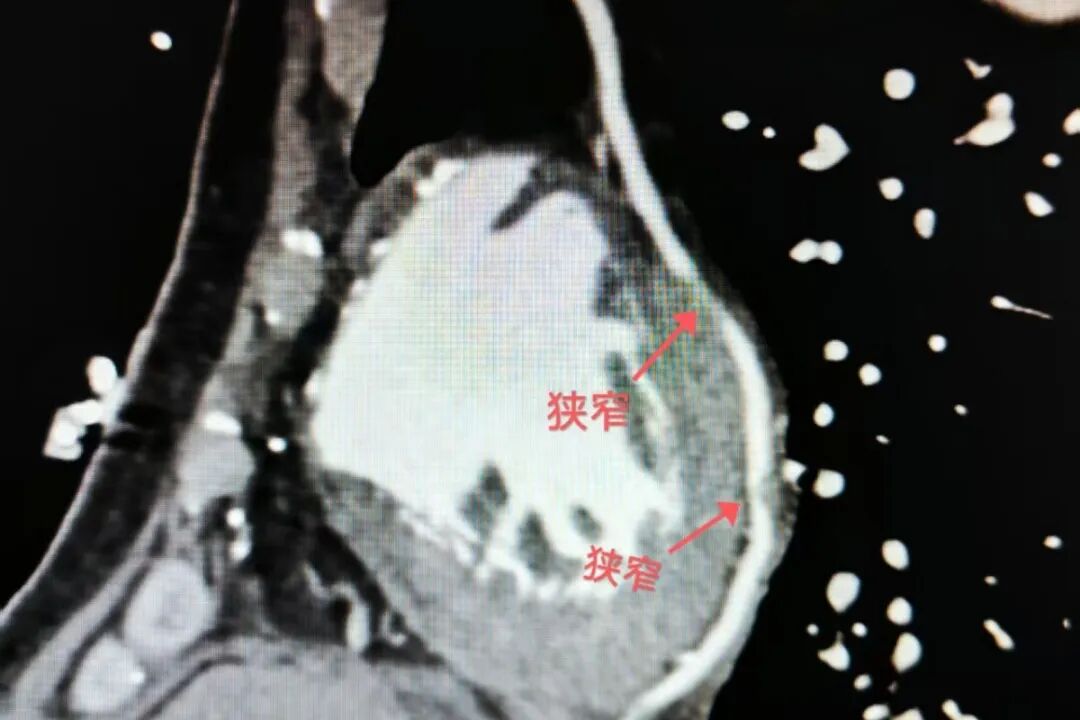

为了帮助周大爷摆脱痛苦,心内科二病区张丽丽副主任医师团队在坚持药物治疗的同时,为他完善了心脏血管CT检查。检查结果不容乐观:当年搭建的3根桥血管仅剩下1根有血流,且这根“幸存”的桥血管也存在严重狭窄;更糟糕的是,周大爷自身的心脏血管条件极差,进一步增加了治疗难度。考虑到老人年事已高,再次实施搭桥手术风险极高,张丽丽与家属充分沟通后,决定先进行造影检查,尽可能找到解决胸痛的突破口。

造影结果比CT显示的更为严峻:周大爷自身心脏的前降支完全闭塞,回旋支存在95%的弥漫性狭窄,右冠远端也已近乎闭塞;仅存的那根桥血管,其远端同样存在严重狭窄,血流受到明显影响。“患者的病情复杂程度超出预期,但我们的目标很明确——不能让老人再忍受这样的痛苦。”张丽丽副主任医师带领冠脉介入团队迅速制定治疗方案,将突破口锁定在仅存的桥血管上。